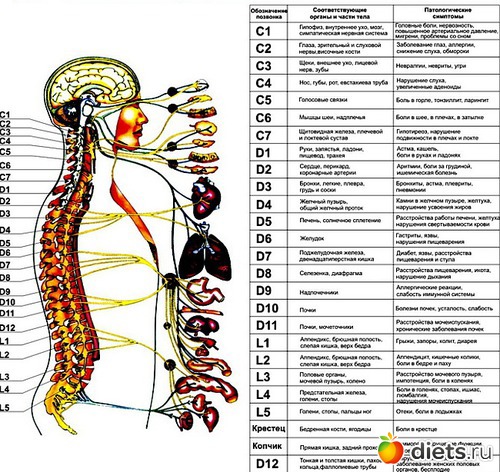

Спинной мозг начинается от головного мозга и заканчивается на уровне промежутка между первым и вторым поясничными позвонками. От спинного мозга отходят нервные корешки, которые ниже уровня его окончания формируют так называемый конский хвост. Корешки конского хвоста участвуют в иннервации нижней половины тела, в том числе тазовых органов. Нервные корешки на небольшом расстоянии проходят в позвоночном канале, а затем выходят из позвоночного канала через фораминарные отверстия. У человека, так же как и у других позвоночных, сохраняется сегментарная иннервация тела. Это значит, что каждый сегмент спинного мозга иннервирует определенную область организма.

Исходя из того что иннервация в теле является сегментарной, мы можем проследить в каком отделе позвоночника есть нарушения, при том или ином функциональном заболевании.

По периферическим нервам нервные импульсы поступают от спинного мозга ко всем органам нашего тела для регуляции их функции. Информация от органов и тканей поступает в центральную нервную систему по чувствительным нервным волокнам. Большинство нервов нашего организма имеют в своем составе чувствительные, двигательные и вегетативные волокна.